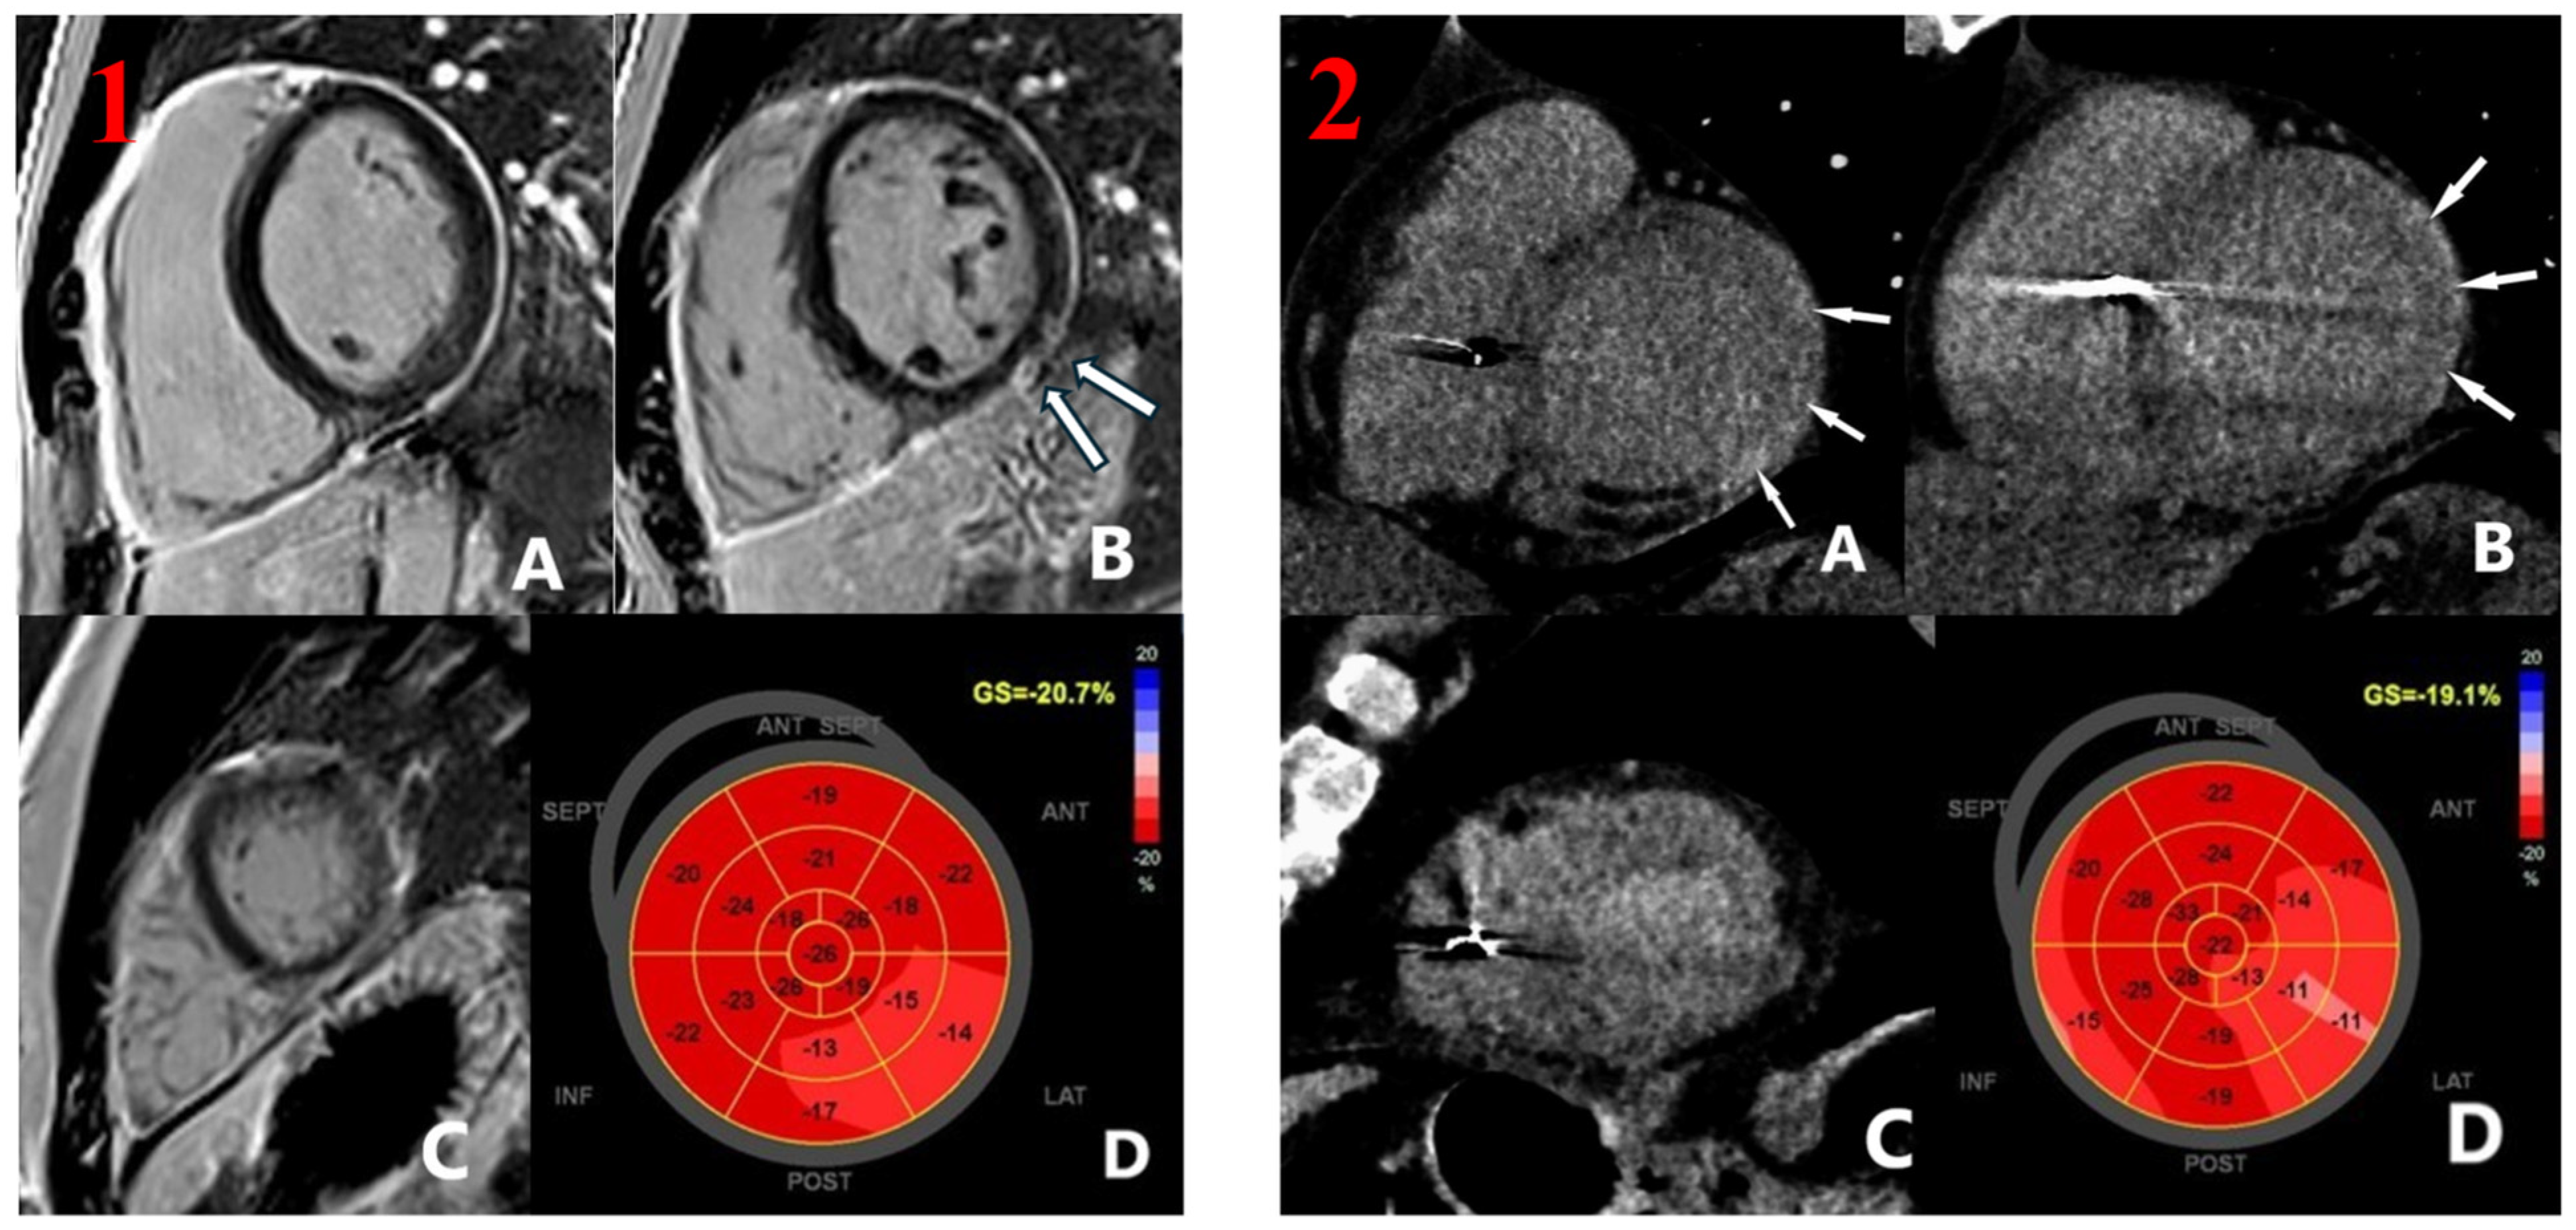

3.4. Late Enhancement and Myocardial Strain Evaluation